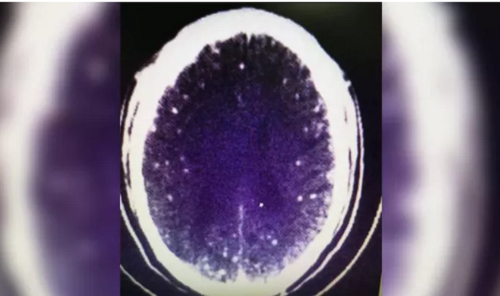

Ăn lẩu với thịt tái bị sán dây chui vào não

Sán dây xâm nhập não người đàn ông khi anh ta ăn thịt không được nấu chín - Ảnh: CNN |

Anh Zhu ở thị trấn Lu Châu, phía Đông tỉnh Chiết Giang, Trung Quốc mua thịt heo và thịt cừu để nấu lẩu cay. Vài ngày sau, anh bắt đầu xuất cảm thấy chóng mặt và đau đầu. Lúc ngủ anh thường có những biểu hiện giống như động kinh.

Sau khi phát hiện sự việc các đồng nghiệp đã nhanh chóng đưa anh đến một bệnh viện gần đó. Kết quả chụp CT não cho thấy anh bị "vôi hóa liên sọ" và tổn thương hộp sọ. Tuy nhiên, vì không muốn tốn tiền nên anh Zhu đã từ chối tiếp tục làm xét nghiệm và về nhà.

Tuy nhiên, sau đó các triệu chứng trên không hề thuyên giảm mà Zhu còn tiếp tục bị co giật. Cuối cùng, anh đến bệnh viện ĐH Chiết Giang để chụp MRI và kết quả là anh bị sán dây lên não.

Khi tìm hiểu biết được gần đây anh Zhu có ăn lẩu, bác sĩ tại bệnh viện nghi ngờ có thể thịt lợn và thịt cừu bị nhiễm ấu trùng sán dây, sau đó xâm nhập vào đường tiêu hóa của Zhu vì thịt không được nấu chín đúng cách.

"Tôi chỉ đun sôi thịt một chút thôi. Đáy nồi đọng lại nước dùng cay có màu đỏ nên tôi không thể kiểm tra được thịt chín kỹ chưa", anh Zhu cho biết

Sau khi được các bác sĩ loại bỏ sán dây sức khỏe của anh Zhu đã hồi phục.